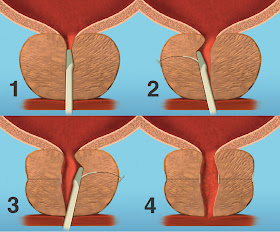

Este fin de semana hemos recibido la visita del Dr. Pippi Salle, que acudió a Madrid a operar con nosotros a un niño de un año de edad con una malformación congénita del pene. Él y el Dr. Enrique de la Peña, el urólogo pediátrico de nuestro equipo en ICUA, operaron al niño con éxito en El Hospital NISA Pardo de Aravaca, de Madrid.

El Dr. Pippi Salle es uno de los genios de la urología actual, ha descrito varios procedimientos quirúrgicos y es uno de los urólogos pediátricos más respetados en el mundo. Es brasileño de origen pero trabaja en Toronto, Canadá.